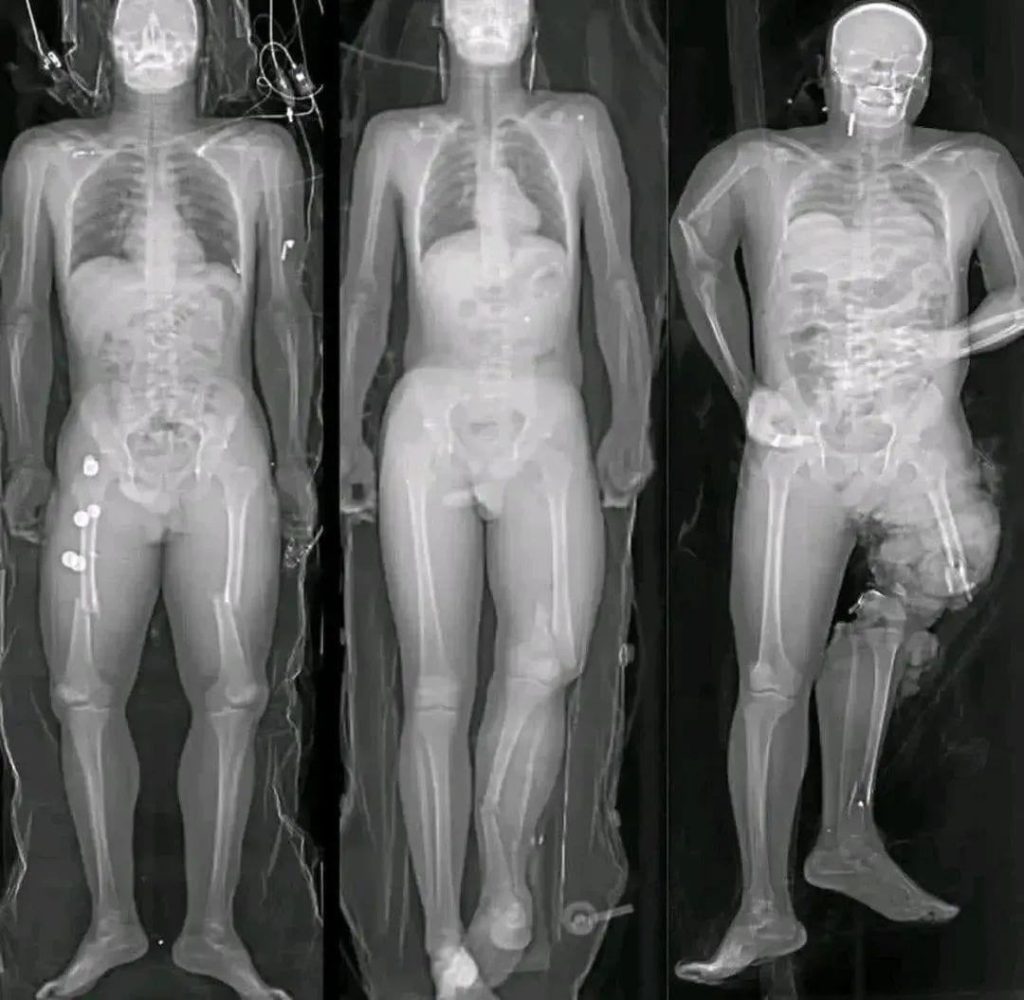

In recent months, a wave of alarming images and short messages has circulated widely across social media platforms, often accompanied by phrases such as “If you got the COVID vaccine, you should know this.” Many of these posts feature dramatic visuals—most notably illustrations of syringes aimed directly at the human heart—designed to provoke fear and urgency. While the images are striking, they rarely provide verified medical context. Instead, they rely on emotional reaction rather than evidence.

The success of these viral messages lies in how they are constructed. Fear-based imagery has always been effective at capturing attention, especially when combined with incomplete or vague warnings. A syringe aimed at a heart immediately suggests danger, even before a viewer reads any accompanying text. This technique taps into a natural instinct to protect oneself from harm.

Another reason these images resonate is that they exploit real but rare medical terms, such as myocarditis, without explaining scale or context. By presenting isolated facts without proportion, they create the illusion of widespread risk where none exists.